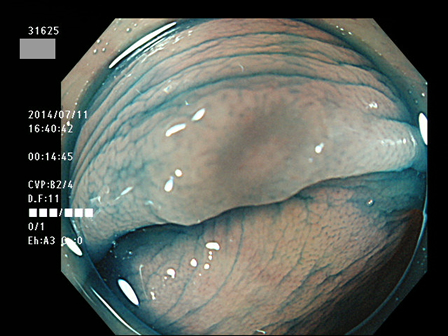

31600 31601 31603 31604 31606  31607 31610 31611 31612 31616 31623 31624 31625 31627 31630 31631 31632 31638 31639 31640 31641 31642 31644 31645 31646 31649 31650 31653 31656 31658 31659 31660 31661 31662 31665 31666 31667 31670 31671 31672 31673 31674 31676 31679 31680 31683 31684 31687 31689 31691 31693 31694 31696 31697 31699 ・・・・の55名

上記100名より抽出した平坦・陥凹型腺腫(=癌化の危険が高いが見落としやすい病変)の内視鏡写真